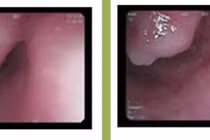

Nội soi tiêu hóa vì nuốt nghẹn, phát hiện khối u thực quản kích thước lớn